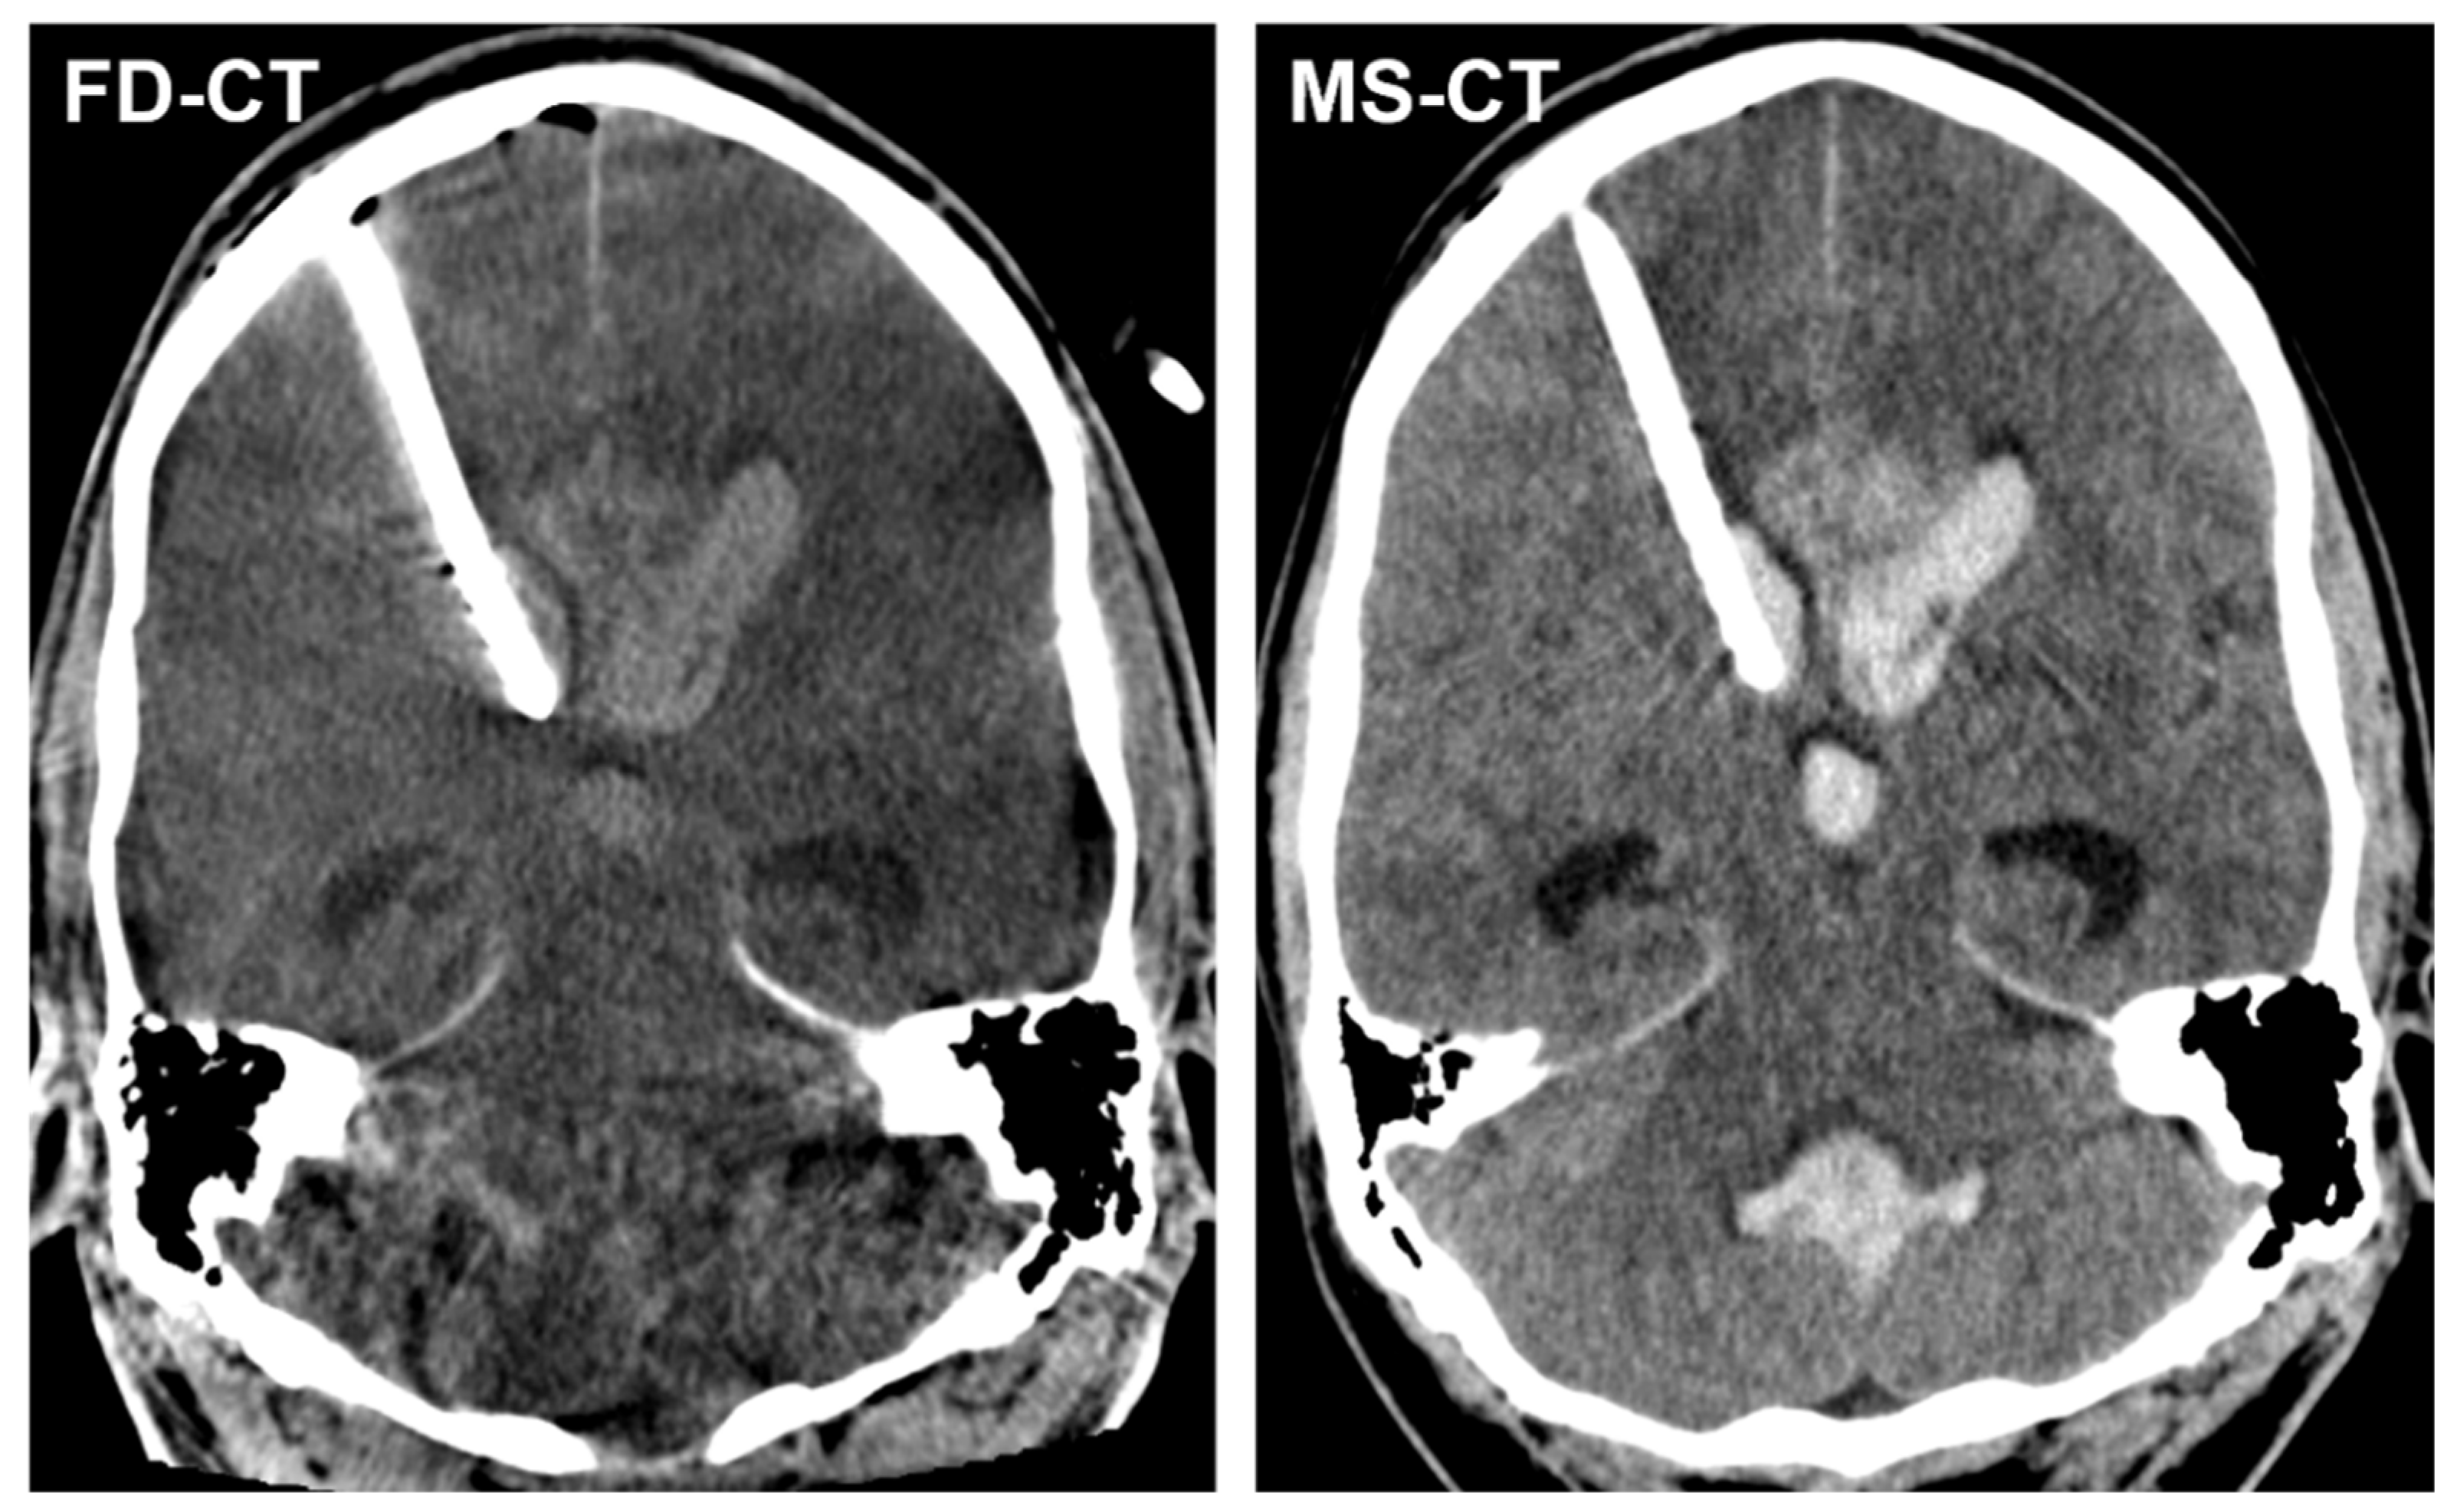

3.3.2. External Ventricular Drain Position

3.3.3. Acute Obstructive Hydrocephalus

3.4. Quantitative Analysis

3.4.2. Modified Graeb Score